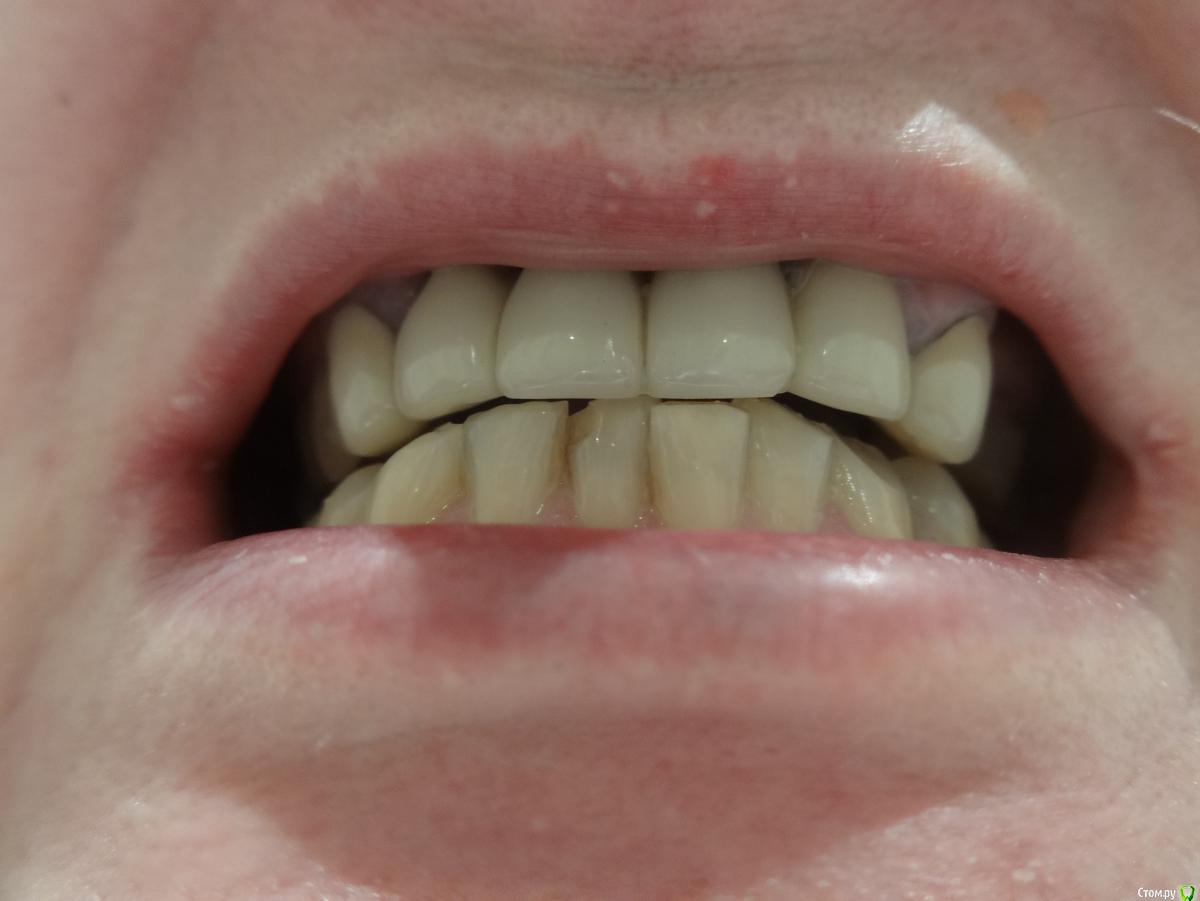

Посоветуйте как мне быть дальше? Пролечила кариес и переделала старые пломбы (снимок до лечения) - даже 8ка нашлась, думала, что все давно поудаляла :).

У меня на верхней челюсти стоит мост из металлокерамики 6 зубов с 13 по 23 делали в 2000 г. Отсутствовали обе единицы. Протезировала несколько раз с 19 лет, была резекция верхушки зуба с кистой сначала одного, потом другого. Затем удалила корни и была попытка наращивания кости гранулами, но прошла неудачно - материал не прижился и от имплантации пришлось отказаться. В итоге, согласилась на мост из МК, но врач настоял на том, чтобы не потерять через некоторое время опорные двойки ставить мост и на клыки. До сих пор жалею, что депульпировала и обточила 4 зуба, чтобы закрыть дыру их двух :(

На нижней челюсти отсутствую жевательные зубы 6,7,8 с обеих сторон и очень давно. Совсем не хочется съемный вариант. Понимаю, что кость атрофировалась в это месте. Есть ли шанс поставить импланты?